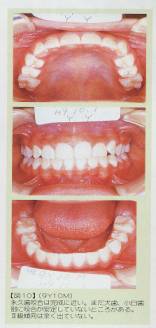

↑永久歯が生えそろった頃です。